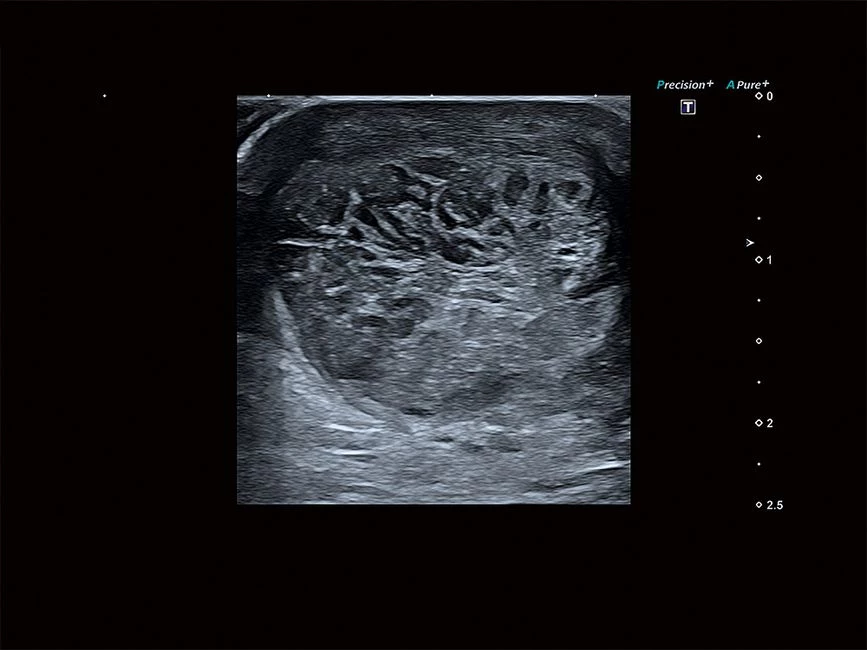

Aplio a550 – это многофункциональная УЗИ система экспертного класса. Высокое качество изображения и интуитивно понятный интерфейс поможет вам обеспечить высокую производительность и скорость проведения исследования.

Система имеет компактные размеры, удобную центральную педаль блокировки, высококонтрастный экран в диагональю 23", регулировка по высоте на расстояние более 36 см, а панель управления и монитор могут быть настроены для любого положения сканирования.

Отличная цветопередача с высокой детализацией и четкостью изображения. Устройство подходит для профессионального использования в частных кабинетах и крупных медицинских центрах. Комплектация сканера применима для самых разных исследований. Широкий диапазон прикладного клинического программного обеспечения высокоэффективен для общих исследований, сердечно-сосудистых, гинекологических, ортопедических, урологических.

Aplio a550 имеет интуитивно понятный пользовательский интерфейс, который упрощает работу во время исследований. В зависимости от режима визуализации, подсказки на экране, комментарии и индивидуальные настройки позволяют оптимизировать и ускорить рабочий процесс.